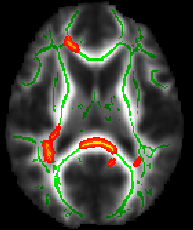

All of the above (apart from setting the skeleton transparency, which has to be done by hand in the GUI) can be carried out with a single command (see first example image):

fslview $FSLDIR/data/standard/MNI152_T1_1mm mean_FA_skeleton -l Green -b 0.2,0.7 tbss_tfce_corrp_tstat1 -l Red-Yellow -b 0.95,1

Alternatively, although showing the stats results on the TBSS skeleton is a true representation of the actual analysis carried out, some people find it easier to visualise the results if the skeletonised results are "thickened" somewhat. In order to make such a presentation easy, there is a script tbss_fill, which thickens the thresholded stats image, filling it out into the local "tracts" seen in mean_FA. For example, to apply this to the same example as above and then view in FSLView on top of the mean_FA image, run:

tbss_fill tbss_tfce_corrp_tstat1 0.95 mean_FA tbss_fill fslview mean_FA -b 0,0.6 mean_FA_skeleton -l Green -b 0.2,0.7 tbss_fill -l Red-Yellow